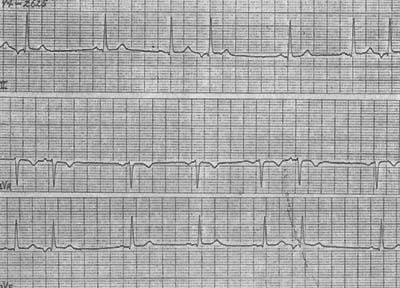

图2 频发房性早搏伴室内差异性传导

频发房性早搏(标记A)提前的畸形P'在前一次心搏T波上,下传QRS波与窦性不同的为室内差异性传导,第一个和第八个标记A其后无QRS波为阻滞性房性早搏